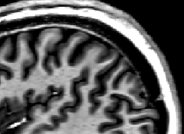

For 3D-readouts in the MP2RAGE sequence, the inversion pulse is sought to be “global”. However, for layer-fMRI applications, we usually need 7T field strengths with “local” RF coils available only. This means, that in the best case scenario, the inversion pulse is played out with a head-only transmit coil. And it can happen that fresh (non-inverted) blood that was outside the coverage of the transmit coil during the time of inversion has flown into the imaging region during the readout modules of the sequence. This inflowing blood is not inverted and mimics magnetization components that would have been already fully decayed back to equilibrium with very short T1 relaxation times. Thus, dependent on the exact choice of the inversion times, there can be very bright voxels at the location of the arterial vessels. This effect has been described in the some of the first human 7T studies and can even be used for vessel segmentation.